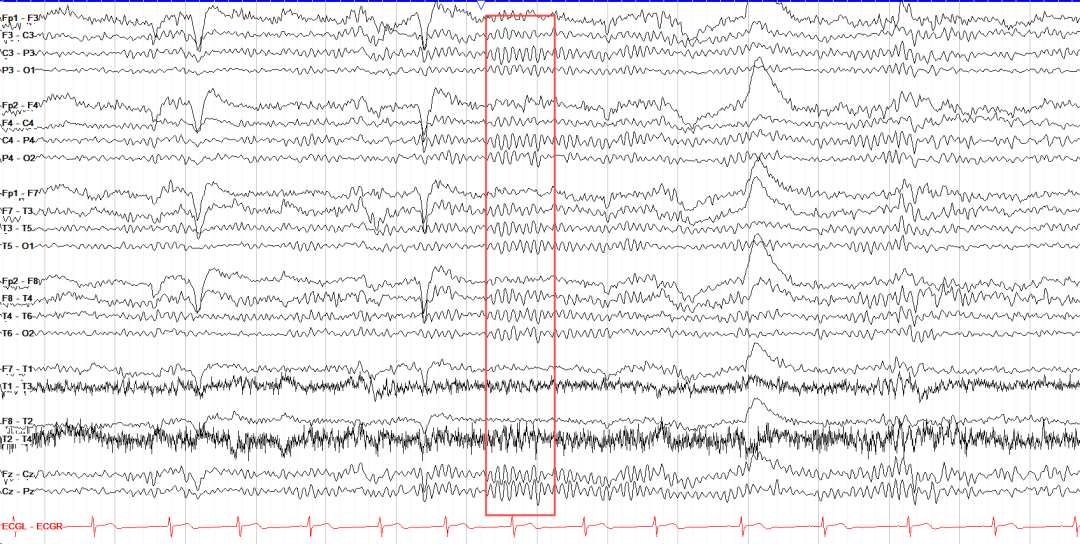

EEG信号特征

波形:EEG 信号波形多样,常见形态包括正弦波(如α波)尖波(如癫痫放电)和棘波(如局灶性异常)。根据脑电波沿基线偏转的次数分为:单相波、双相波和三相波;根据波形分为:正弦样波、多形性波、弓形波(梳状波)、棘波、尖波;由2个或2个以上相连续的波组成复合波:棘慢复合波、尖慢复合波、多棘波、多棘慢复合波等。

出现方式(节律性、连续性、同步性、对称性):正常的α节律具有明显的节律性呈现规则的正弦波形态;而异常脑电图可能会出现节律紊乱的情况。连续性方面,正常脑电图的背景活动一般具有一定的连续性,若出现中断或异常的间歇,则可能是异常表现。同步性指不同脑区的EEG信号在时间上的一致性,如α节律在双侧半球通常具有较好的同步性;对称性则是指EEG信号在双侧大脑半球对应区域的相似程度,正常情况下,双侧半球的EEG信号在频率、振幅和波形等方面应基本对称,若出现不对称,可能提示存在神经系统疾病。

波形持续时间:棘波(<70 ms)与尖波(70-200 ms)的区分对癫痫诊断至关重要;睡眠纺锤波持续0.5-2秒,是N2期睡眠的标志。

相位同步性:跨脑区相位同步(如θ-γ跨频耦合)与记忆巩固相关;病理状态下(如癫痫发作)可能出现全脑相位同步异常。